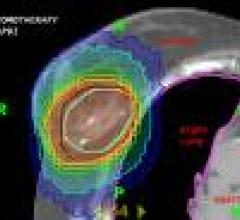

February 19, 2010 - At Roseville Radiation Oncology Center (ROC) at Radiological Associates of Sacramento (RAS), a large private medical group, which treats 30-35 patients per day, mainly with prostate and breast lesions, doctors treated patients using volumetric modulated arc therapy (VMAT).

February 15, 2010 - New data released shows targeted radiotherapy, using real-time prostate tumor tracking during external beam radiation, enables the delivery of high doses of radiation, while reducing treatment-related side effects, including bowel urgency, rectal irritation and urinary irritation.